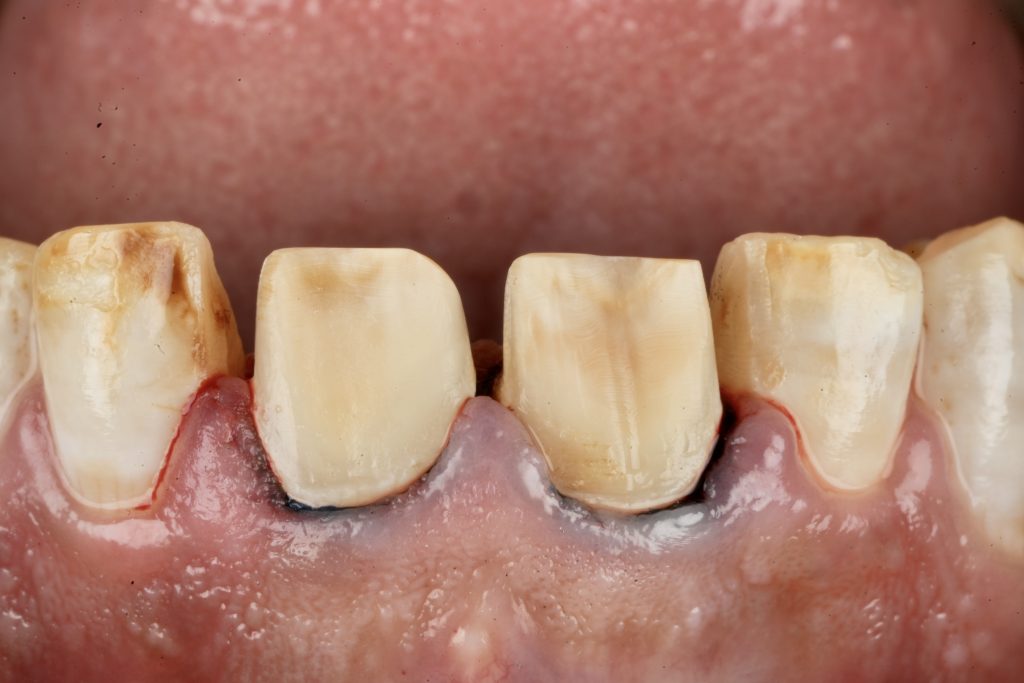

Using silicone indexes derived from the mock-up, controlled minimal-thickness veneer preparations (0.3–0.5 mm) were carried out under microscope magnification to ensure uniform reduction and margin clarity (Fig 2). Finish lines were placed juxta-gingivally with soft-tissue protection using Teflon and double-cord isolation.